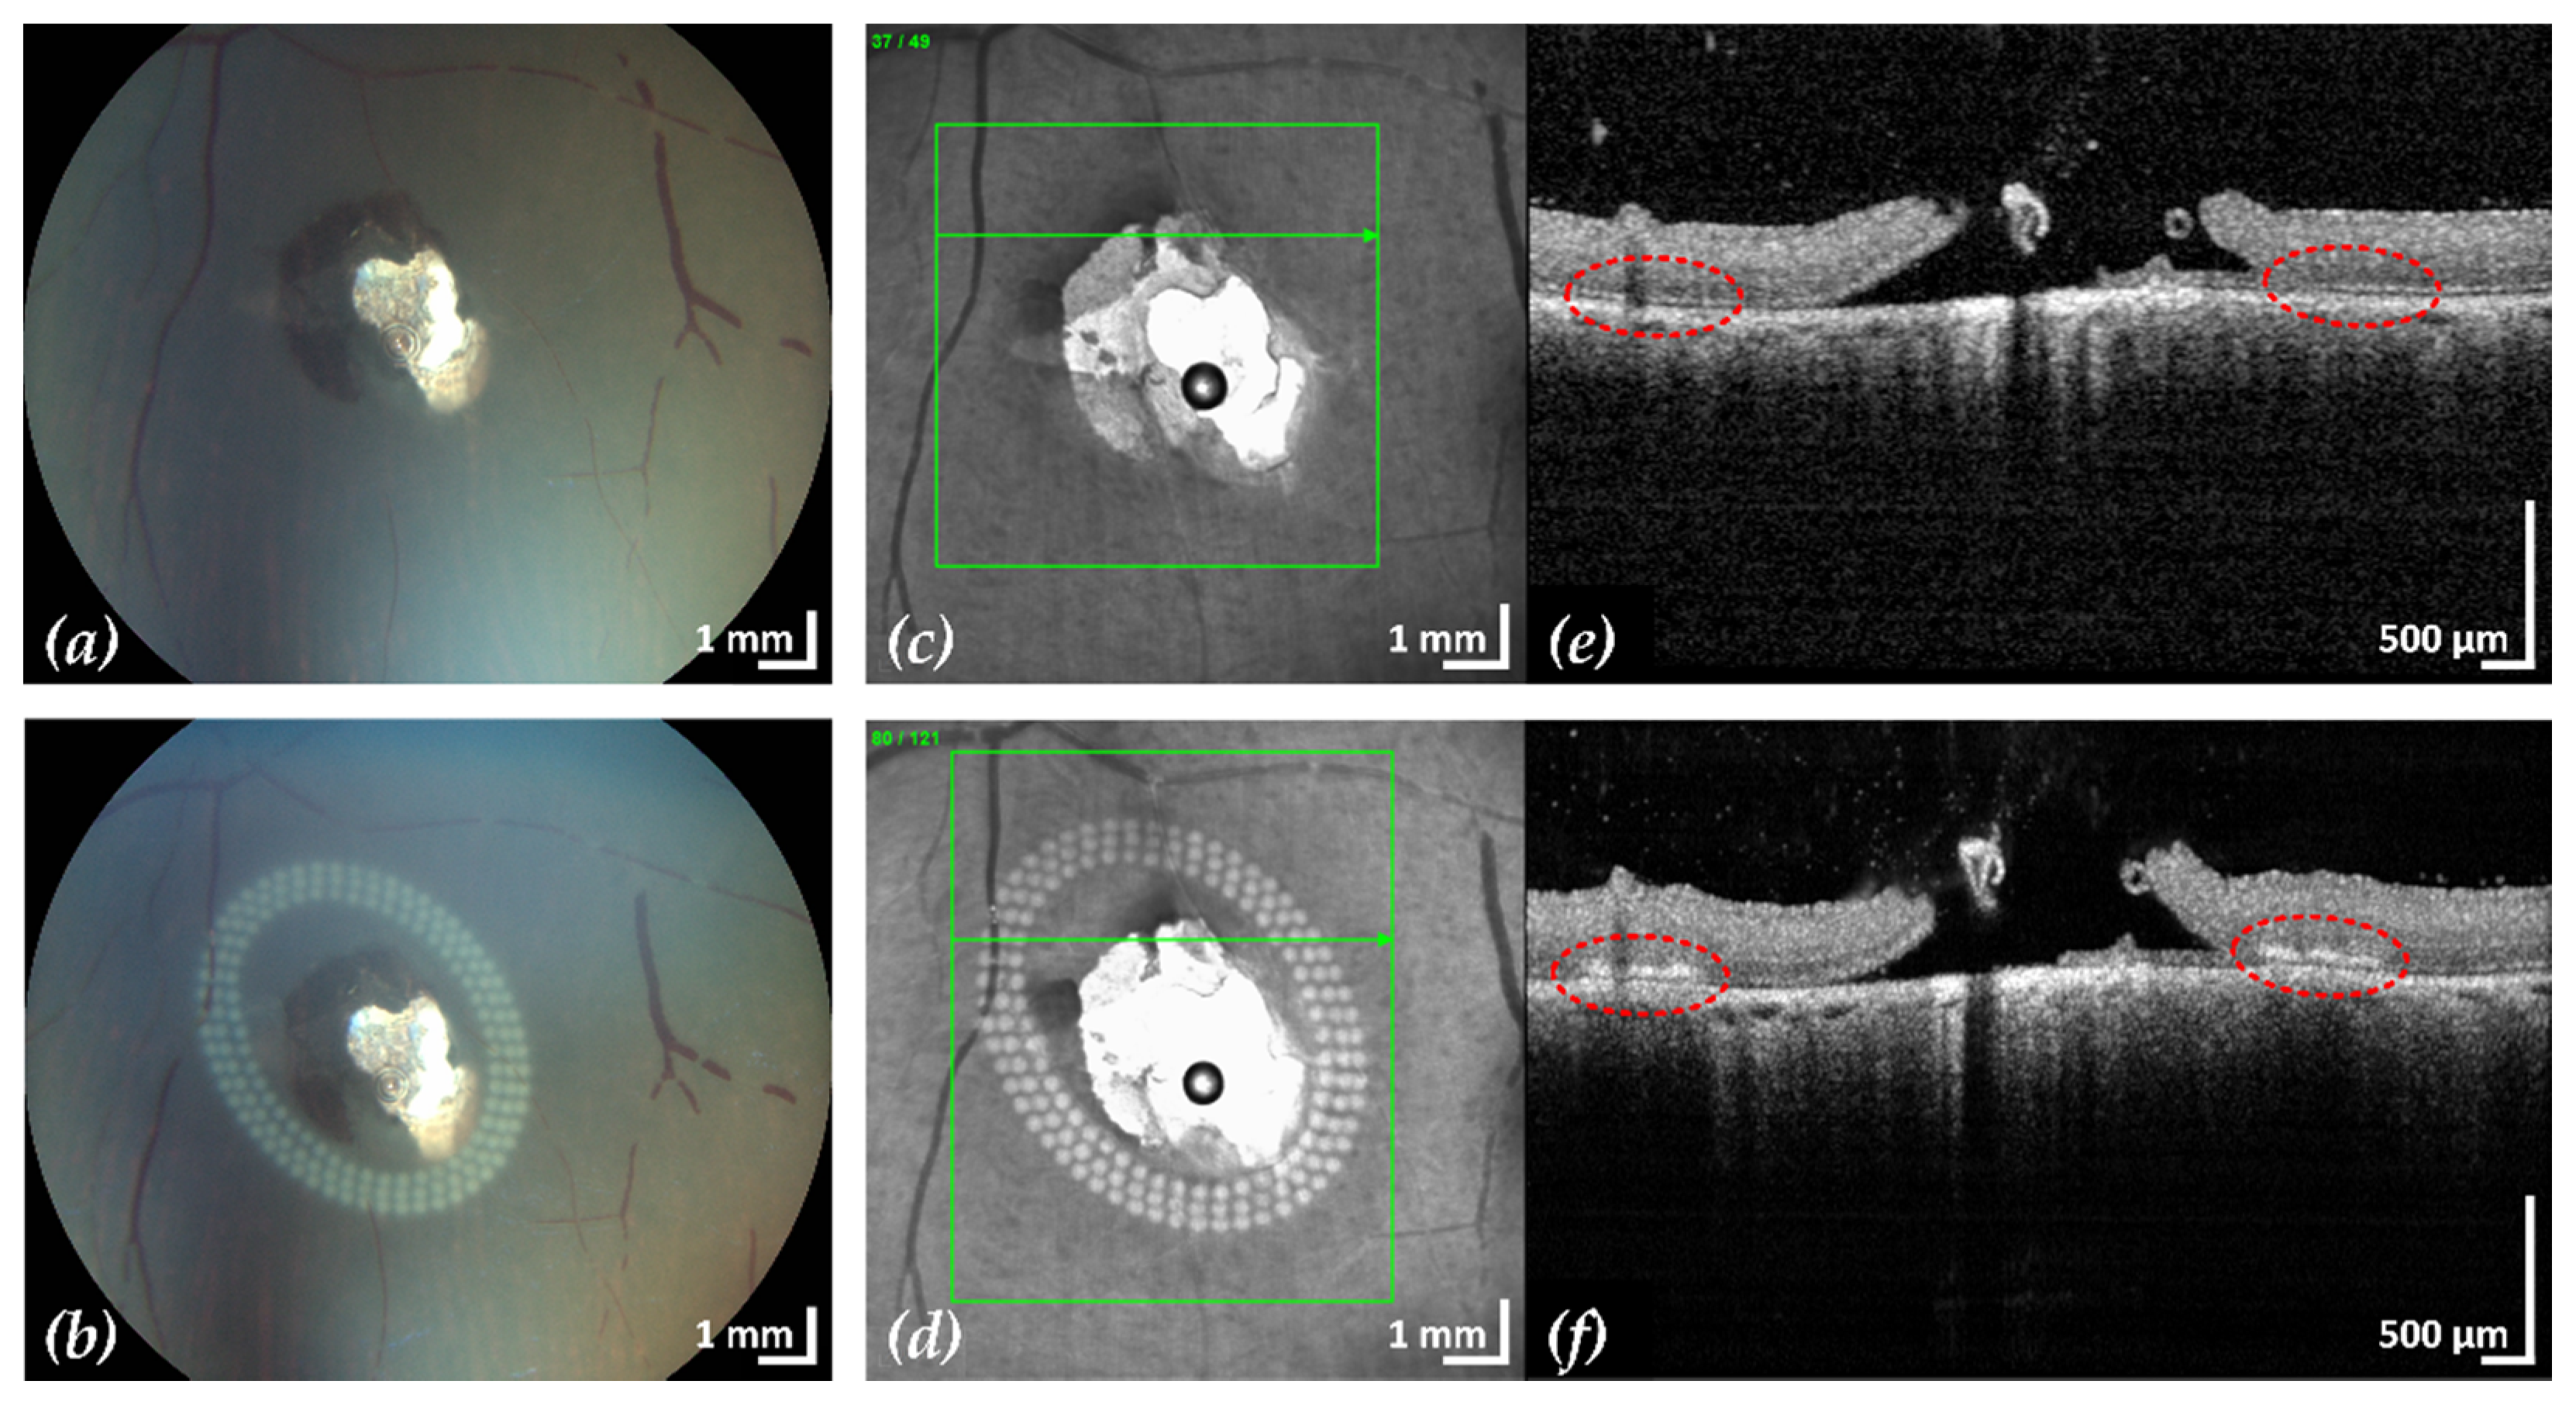

Figure 5. Example 2: treatment outcome in ex-vivo porcine eye with artificially induced retinal break (area of retinal break and adjacent RD: 15.4 mm2). Fundus photographs before (a) and after (b) treatment, infrared scanning laser ophthalmoscope images before (c) and after (d) treatment with the corresponding SD-OCT B-scans (e,f). A total of 153 lesions were applied in three rows with a radial and tangential (point to point) distance of 200 µm and 300 µm, respectively. The LPC treatment time was 2:11 min. The effect of LPC treatment is visible in (b,d) as spots of whitened tissue and in (f) as ruptures in the retina at the treatment sites (red).